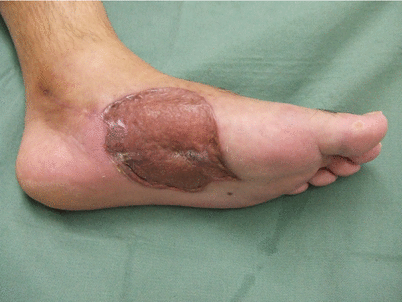

Photo is of sore that still re-occurs 5 years after surgery.